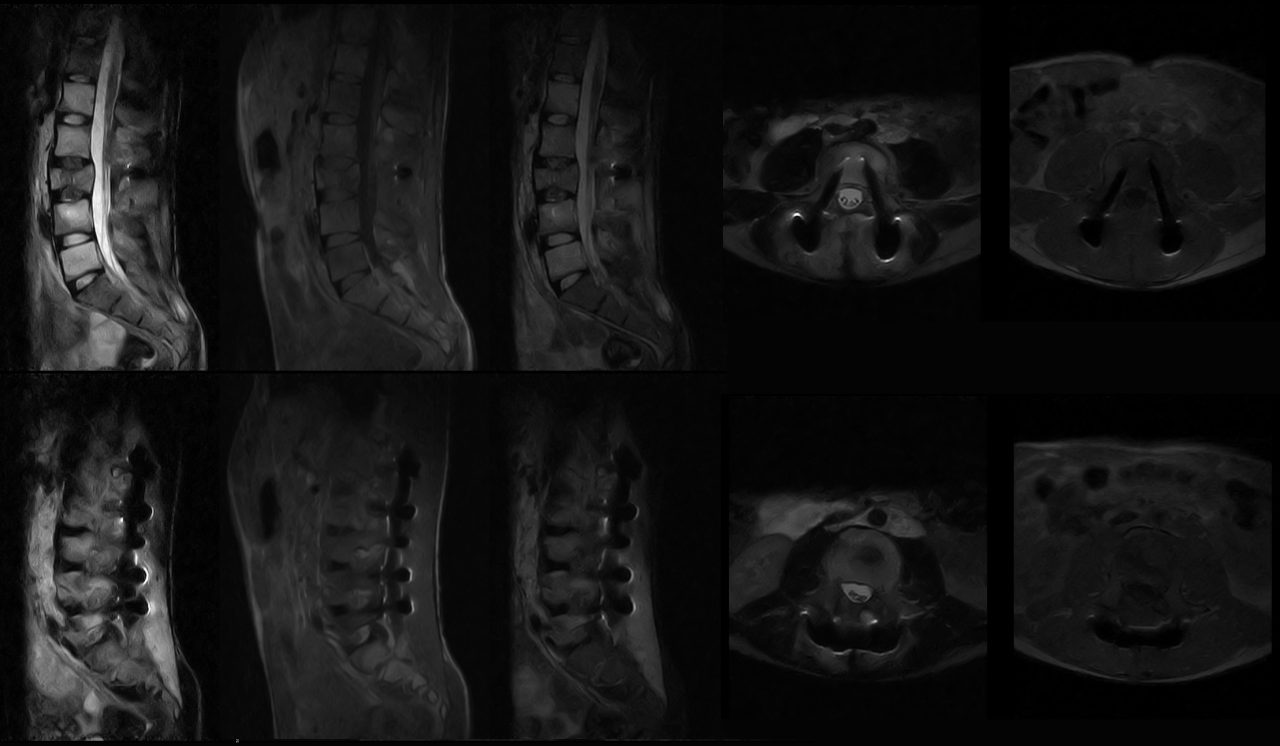

Os implantes metálicos podem criar artefatos nas imagens de ressonância magnética, como áreas escuras ou claras que não correspondem à realidade anatômica do paciente. Além disso, a presença de metais pode causar aquecimento localizado nos tecidos, representando um risco para a segurança do paciente. Esses desafios têm limitado o uso efetivo da ressonância magnética em pacientes com implantes metálicos, resultando em alternativas menos precisas ou invasivas para o diagnóstico médico.

A ressonância magnética de campo aberto e baixo campo é uma abordagem inovadora que promete superar os desafios da ressonância magnética tradicional em casos de presença de implantes metálicos. Nesse tipo de equipamento, o campo magnético é gerado por ímãs permanentes de baixa potência, o que reduz a interferência dos metais e minimiza as distorções nas imagens.

1. Imagens de alta qualidade: A ressonância magnética de campo aberto e baixo campo permite a obtenção de imagens de alta qualidade. Isso é possível graças aos avanços na tecnologia de processamento de sinal, que compensa as distorções causadas pelos implantes metálicos.

1. Menos distorções nas imagens: A interferência causada pelos implantes metálicos é minimizada na ressonância magnética de campo aberto e baixo campo, resultando em menos distorções nas imagens. Isso permite que os médicos obtenham uma visão mais precisa e detalhada das estruturas internas do corpo humano, facilitando o diagnóstico e o planeamento do tratamento.